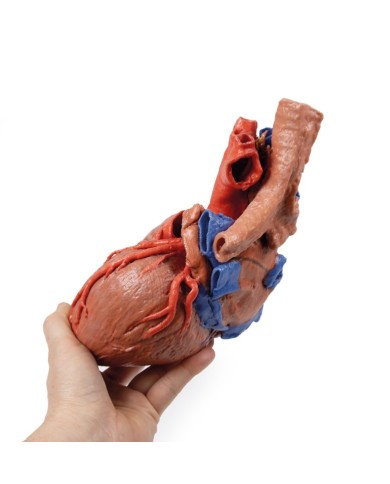

Modello di cuore di alta qualità scomponibile in 5 parti

Modello di cuore di alta qualità scomponibile in 5 parti

La parete anteriore del cuore è staccabile per poter vedere i ventricoli.

Realizzato in stampa 3D ad elevatissima risoluzione a colori.

Realizzato in stampa 3D ad elevatissima risoluzione a colori.

Realizzato in stampa 3D ad elevatissima risoluzione a colori.